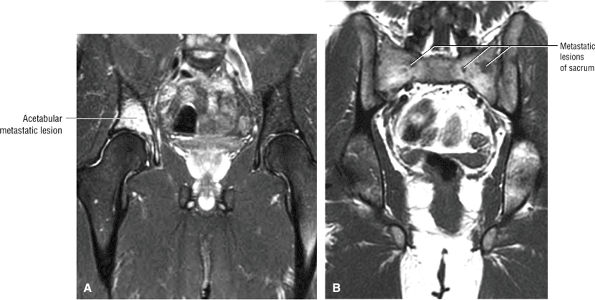

A bump-osteophyte complex (Fig. 3.186) where the dysplastic femoral bump is anterior to the lateral to posterolateral osteophyte as visualized on coronal MR images, and the osteophyte may demonstrate hyperintense edema on FS PD FSE sequences

-

Fibrocystic change (Fig. 3.187) (herniation pits), which commonly occurs either anterior to the dysplastic bump (bump-cyst concordance) or anterior to the dysplastic bump (bump-cyst discordance) and is the result of flexion-induced pressure and not normal invagination of synovium210